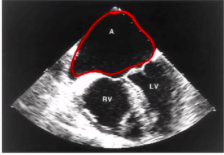

What is a common atrium?

-